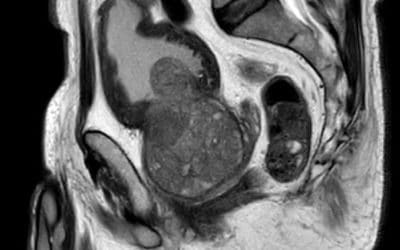

Déroulement et role de l’IRM prostatique

L'IRM de la Prostate : Déroulement de l'Examen et Son Rôle dans le Diagnostic de la Prostatite et...